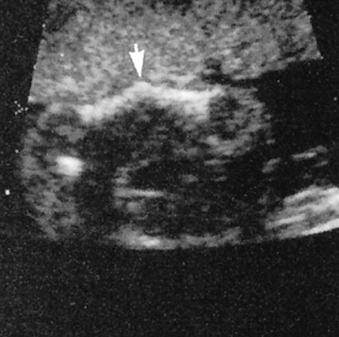

unilateral pulmonary agenesis/hypoplasia